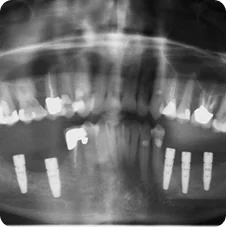

Post-operative Implant Placements

Impressions #18, 19 and 20

Impressions #30 and 31